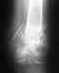

Я съездил в отделение УНИИТО на Студенческой 12 на консультацию. Ознакомившись со снимками, доктор сказал что или гипс и когда нибудь срастется, или дополнительный шуруп.

Спросил надо ли освежать по новой концы перелома. Мне ответили что не надо. То есть получается процесс регенерации возможен дальше?

Да, смысл наложения гипсовой повязки довольно призрачный. И, скорее всего, добиться сращения можно без обнажения концов отломков.

Надо уточнить особенности ситуации путем осмотра и дополнительных снимков, тогда будет больше оснований для выбора дальнейших действий.